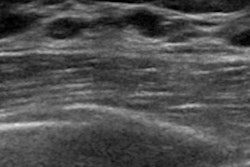

But the diagnostic accuracy of the modality is tied to the skill and experience of the operator. Research has demonstrated that using CAD with ultrasound can mitigate user variability, yet there have been few studies examining how CAD affects the diagnostic performance of readers with differing breast imaging experience (Medicine, January 2019, Vol. 98:3, p. e14146).

Park's team investigated the value of a CAD program applied to diagnostic breast ultrasound based on operator experience. The group used ultrasound images of 100 breast masses acquired from 92 women between May and June 2015; three less-experienced (first-year fellowship trainees) and two experienced (eight to 10 years) breast imaging radiologists analyzed the ultrasound features of the breast masses without and with CAD, using BI-RADS categories.

Of the 100 breast masses, 41% were malignant and 59% were benign. Overall, CAD helped less-experienced readers improve their diagnostic performance across all measures, while it improved the specificity and positive predictive value of the experienced readers.